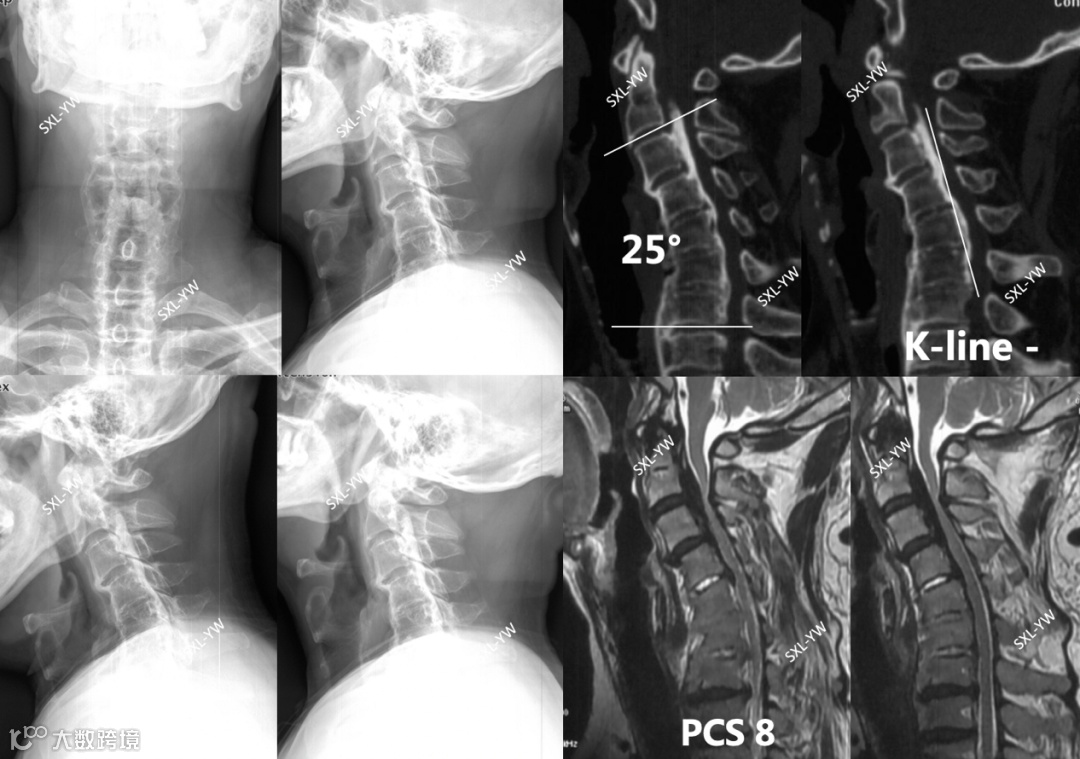

图14 K线与PCS评分的正面碰撞之二,术前影像。后凸25°、K线阴性,如果参考K线理论,这些都是单开门手术的禁忌、单开门术后脊髓漂移将不充分,事实会真的如此吗?该患者PCS评分为8分,单开门术后神经功能恢复的可能性大,建议行单开门手术。2个截然不同的指导意见,哪个才是正确的?

图15 K线与PCS评分的正面碰撞之二,术后影像。C1-7单开门术后脊髓获得充分漂移,后凸不影响脊髓漂移程度

上述病例证实:K线不能预测单开门术后脊髓漂移情况及神经功能的恢复情况;脊髓漂移程度与K线没有相关性;PCS评分具有预测神经功能恢复情况、指导手术方式选择、明确手术范围的作用。